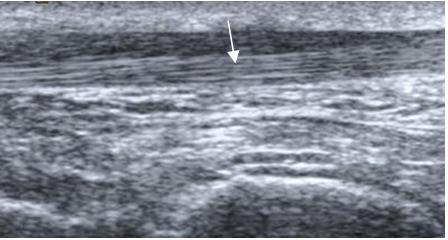

En ecografía, los ligamentos son estructuras lineales e hipoecoicas, con un espesor menor a 2 mm. (4). (Fig 9 y 15).

Fig 15. Ligamento tibiocalcáneo normal en ecografía, corte sagital.

Fig 16. Ligamento tibiocalcáneo normal.

A: RM axial y B: RM coronal en T1.